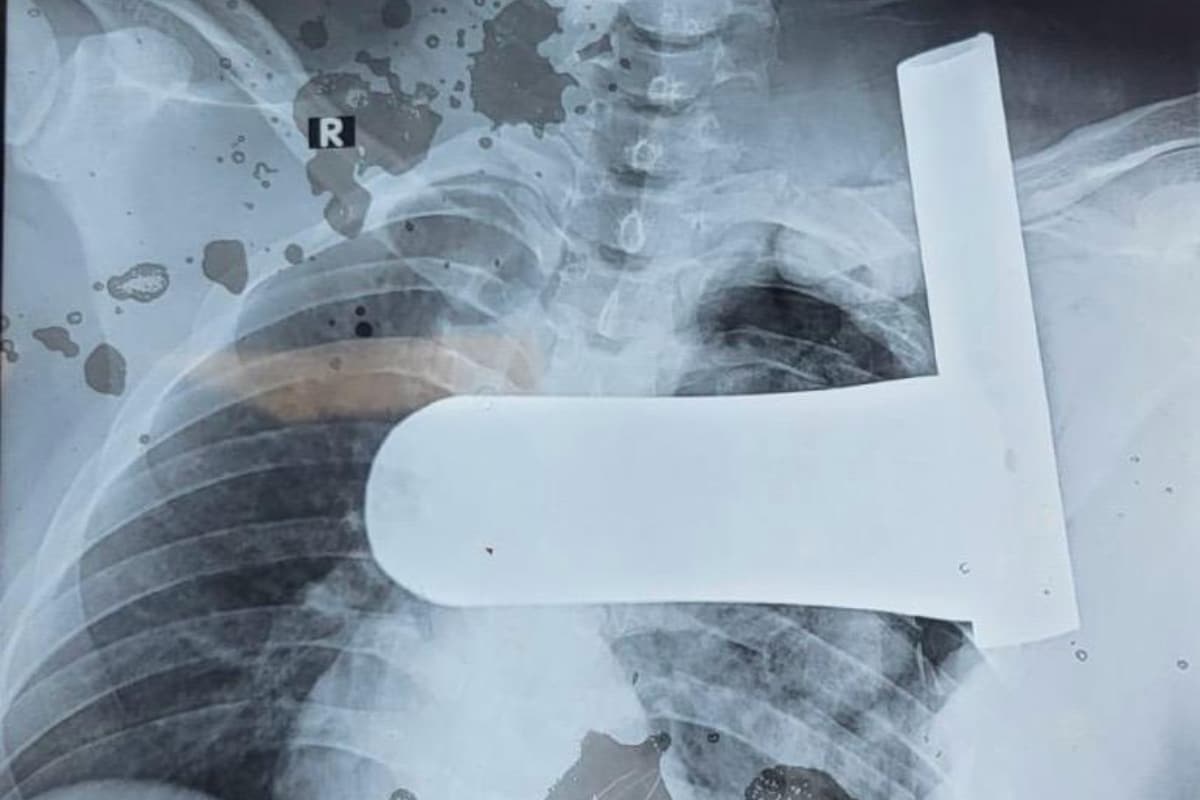

गंभीर हालत में युवक को अत्यधिक रक्तस्राव और शॉक की स्थिति में आरएनटी मेडिकल कॉलेज लाया गया. सीटी स्कैन में सामने आया कि यह मोटा पाइप पसलियां तोड़ते हुए फेफड़े को चीरकर गर्दन तक पहुंच गया था. रेडियोलॉजी विभाग के प्रोफेसर डॉ. कुशल गहलोत ने बताया कि इससे सबक्लेवियन धमनी और शिरा भी क्षतिग्रस्त हो गई थीं, जिससे फेफड़ों में भारी रक्तस्राव हो गया था.

मरीज की सीटी स्कैन रिपोर्ट.

कार्डियोथोरेसिक सर्जन डॉ. विनय नैथानी के नेतृत्व में डॉक्टरों की टीम ने तुरंत ऑपरेशन शुरू किया. जटिल सर्जरी के दौरान एल-आकार के पाइप को सावधानीपूर्वक बाहर निकाला गया. साथ ही क्षतिग्रस्त रक्त वाहिकाओं की मरम्मत, फेफड़े का उपचार और टूटी पसलियों का पुनर्निर्माण किया गया. सफल ऑपरेशन के बाद मरीज की हालत अब स्थिर है और वह तेजी से स्वस्थ हो रहा है. आरएनटी मेडिकल कॉलेज के प्रिंसिपल डॉ. राहुल जैन ने बताया कि इस तरह के मामलों में मृत्यु दर बहुत अधिक होती है, लेकिन समय पर इलाज और टीमवर्क से एक जीवन बचाया जा सका.